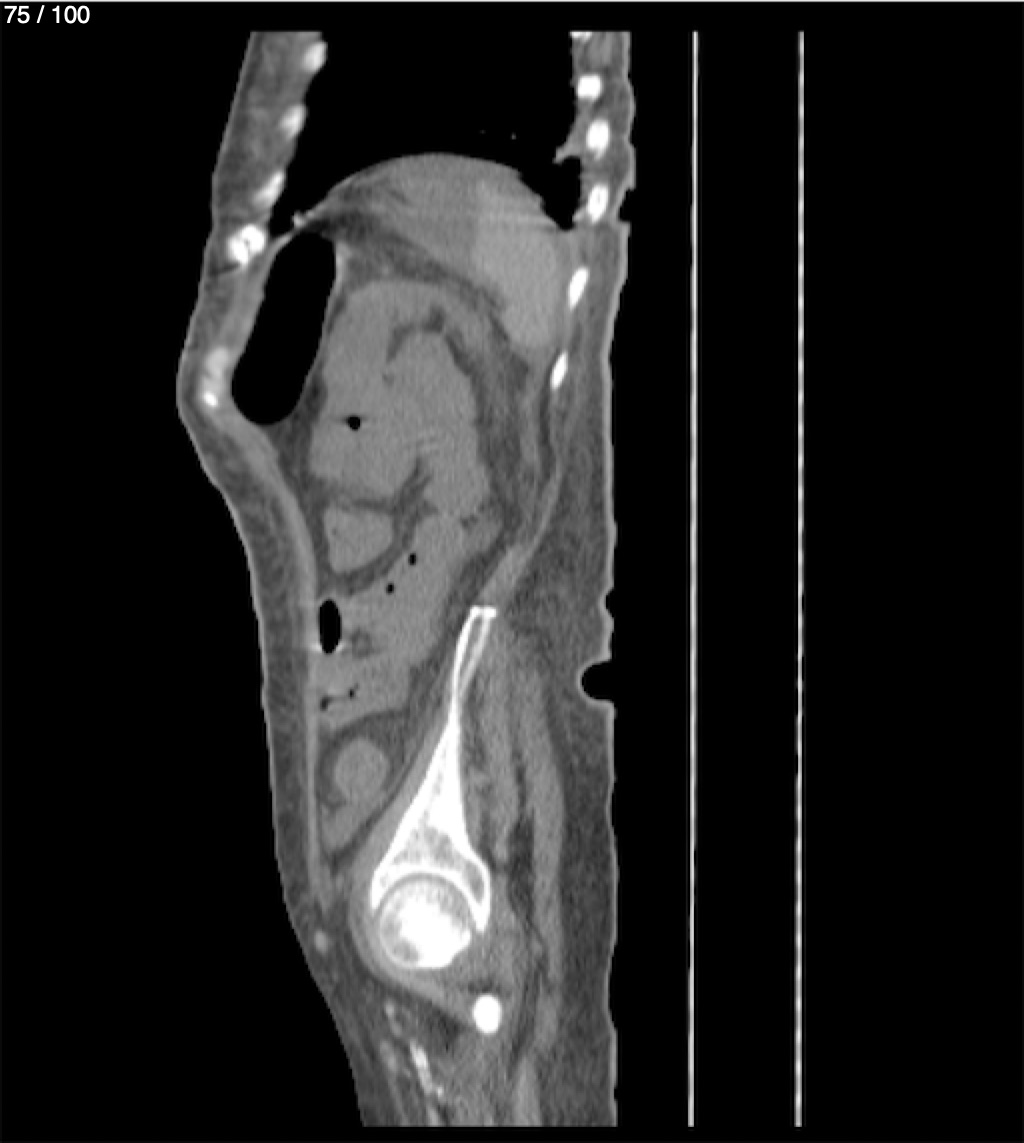

Hilda Geronimo Mendez 60A - T.C Abdomen Simple